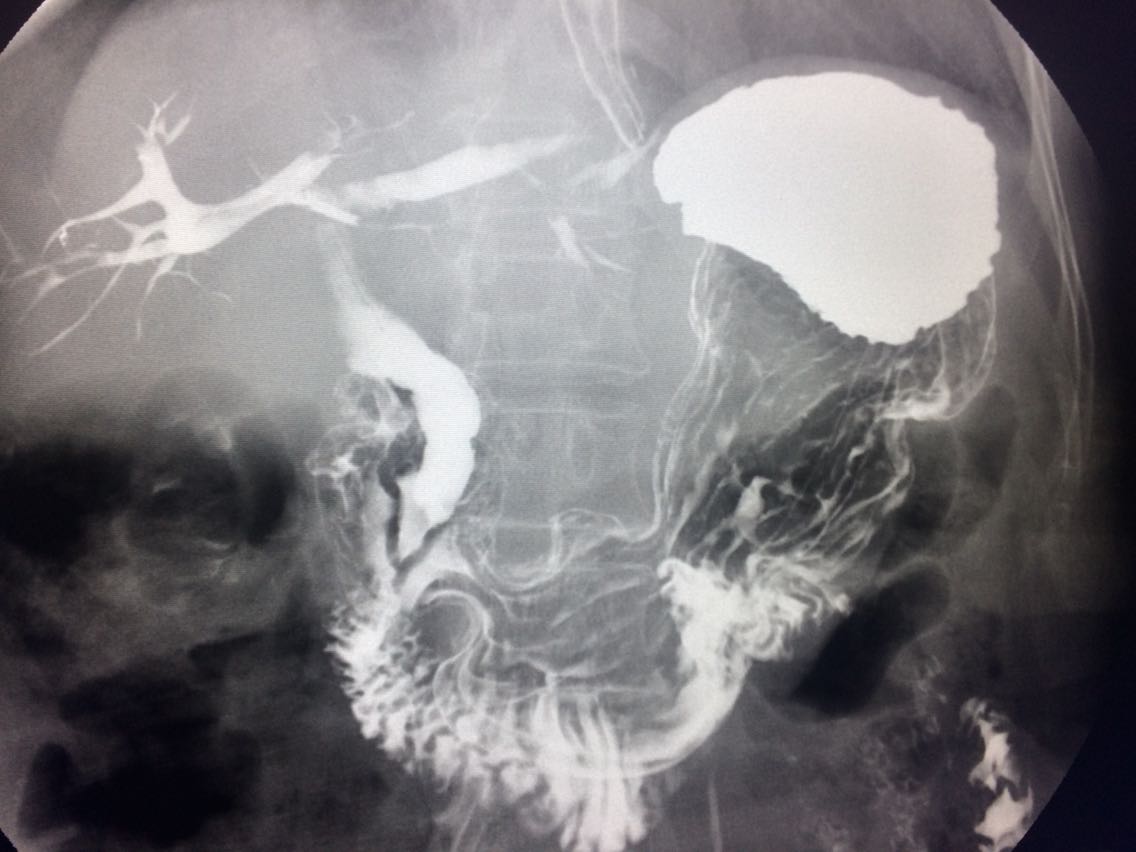

查体未见明显异常。 上消化道造影如图。

诊断食管癌。 造影剂逆流入胆道。

讨论食管癌的分型? 造影剂逆流的原因及处理方法?